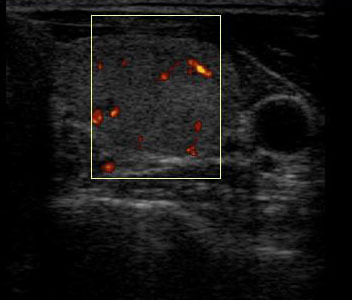

Кровоток в узле

Узел по структуре изоэхогенный с четкими контурами и ободком Halo. По данным допплеровского исследования кровоток в узел смешанного типа - перинодулярный и интранодулярный.